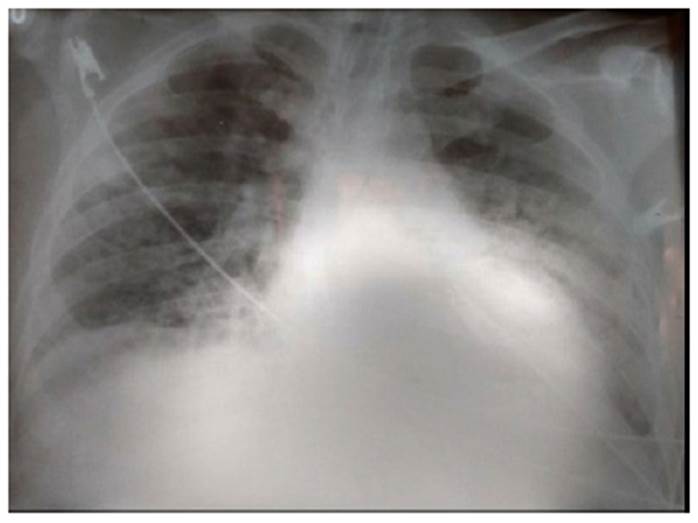

El paciente ingresó a la Unidad de Cuidados Intensivos con los siguientes diagnósticos: insuficiencia respiratoria, sepsis por infección por COVID-19 y diabetes mellitus 2 compensada. Se planteó la siguiente terapéutica: nada por vía oral, ClNa 90/000 + ClK 20 % (EV a 80 cc/h), ceftriaxona 2 g (EV c/24 h), azitromicina 500 mg (SNG c/24 h), ivermectina 80 gotas (SNG c/24 h), vitamina C 2,5 g (EV c/12 h), zinc 30 mg (SNG c/12 h), paracetamol 1 g (EV condicional a T > 38,5 °C), hemoglucotest (c/8 h), soporte de oxígeno, control de funciones vitales, balance hidroelectrolítico y con estrategia respiratoria de pronación. Al inicio del segundo día de hospitalización, presenta hemodinamia estable, la cual se deteriora de manera espontánea y progresiva; al promediar el medio día, presenta disminución de la saturación de 95 % a 60 %, FR: 46 veces por minuto, FC: 105 por minuto, PA: 150/97 mmHg, encefalopatía, agitación psicomotriz, cianosis central y periférica, signos de hipoperfusión, y con caída brusca del PO₂; además, presenta enfisema subcutáneo en la región cervical. Debido a la inestabilidad, se protege la vía aérea con intubación endotraqueal. La tomografía helicoidal multicorte de tórax muestra una imagen de neumomediastino espontáneo (Figura 2) que se extiende a las zonas cervical y abdominal (Figura 3), y se evidencia el efecto Macklin espontáneo.

Figura 2 Tomografía helicoidal de tórax, corte transversal. Se observa el enfisema subcutáneo y el neumomediastino que limita el espacio de la cavidad cardiaca